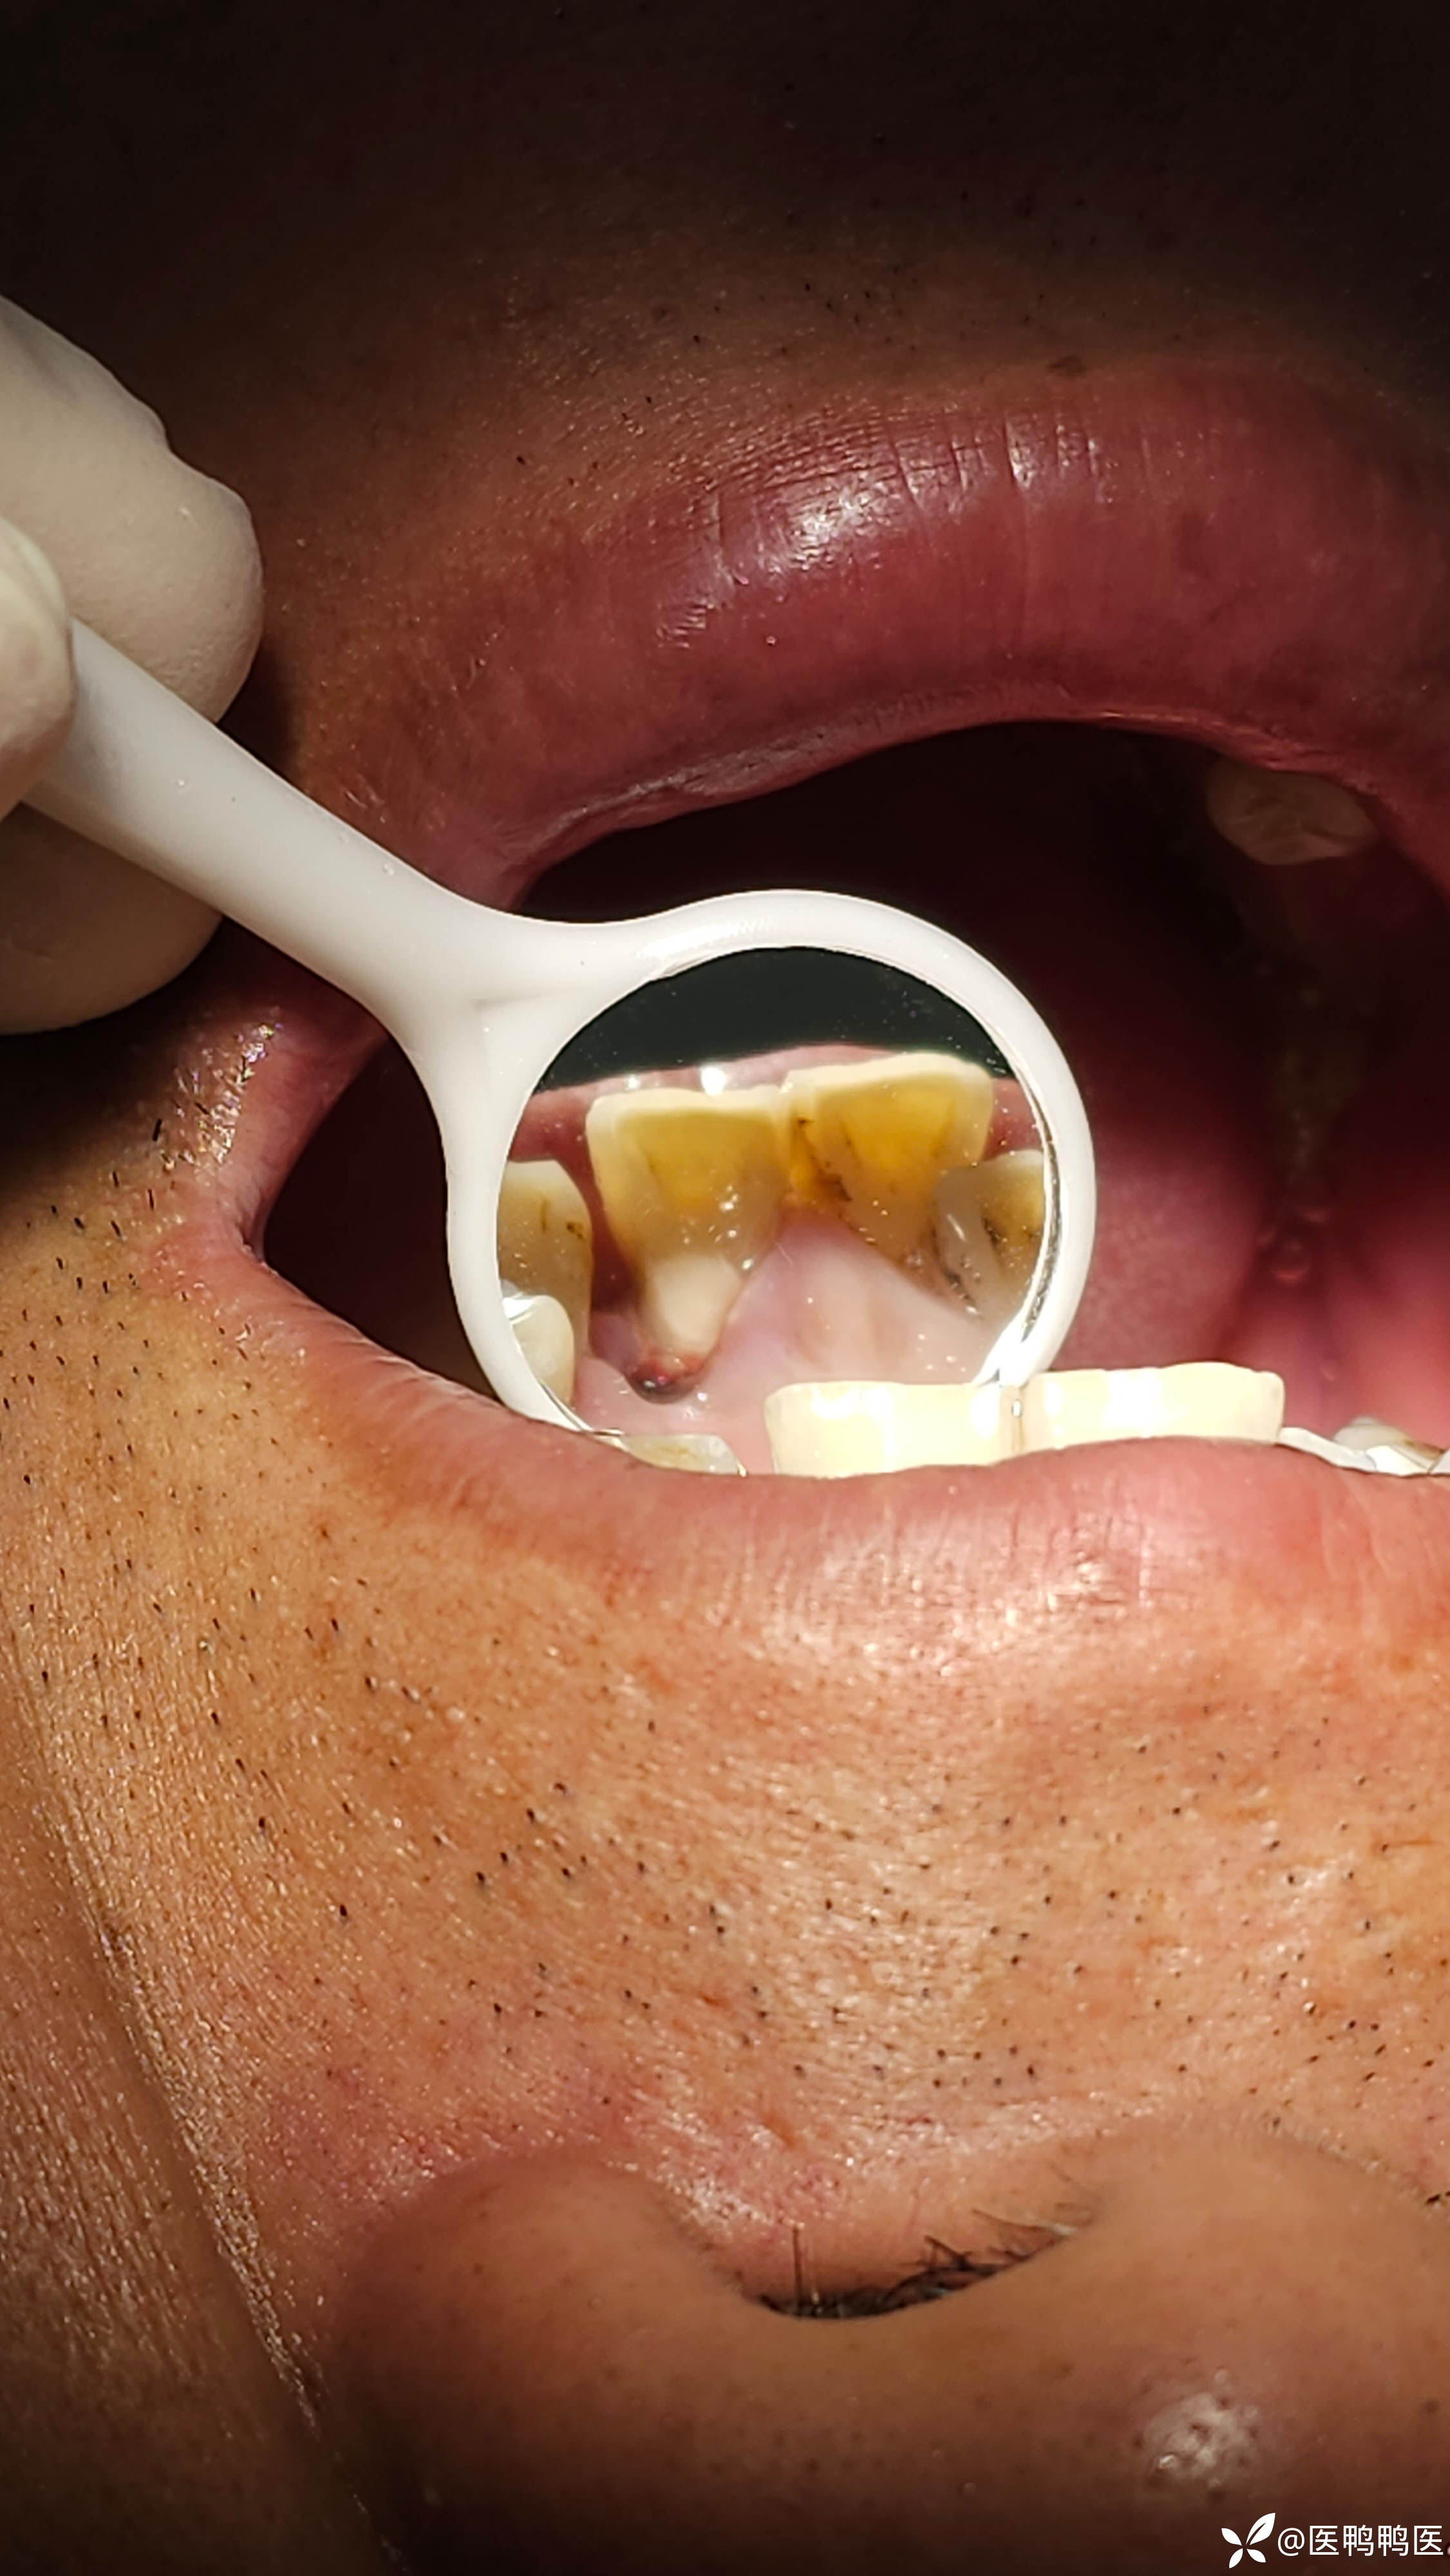

老板说留 就留吧 我是个以老板为主见的 有主见医生

情况就是这么个情况,具体情况还要看具体情况

告知患者只能看 不能用

龋齿 (53)